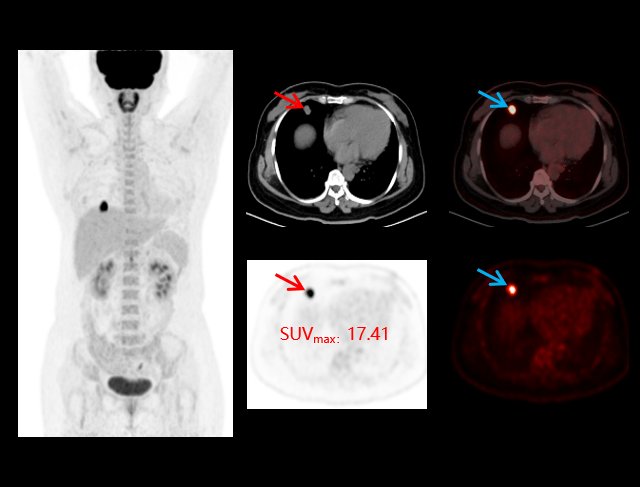

Limfom

Tehnologia PET/CT digitală joacă un rol crucial în diagnosticarea și monitorizarea limfomului, oferind imagini de înaltă rezoluție pentru detectarea leziunilor și evaluarea eficienței tratamentului.

Cancer pulmonar

Investigațiile cu PET/CT digital oferă o evaluare precisă a cancerului pulmonar, sprijinind diagnosticarea timpurie, stadializarea corectă și monitorizarea răspunsului la tratament.